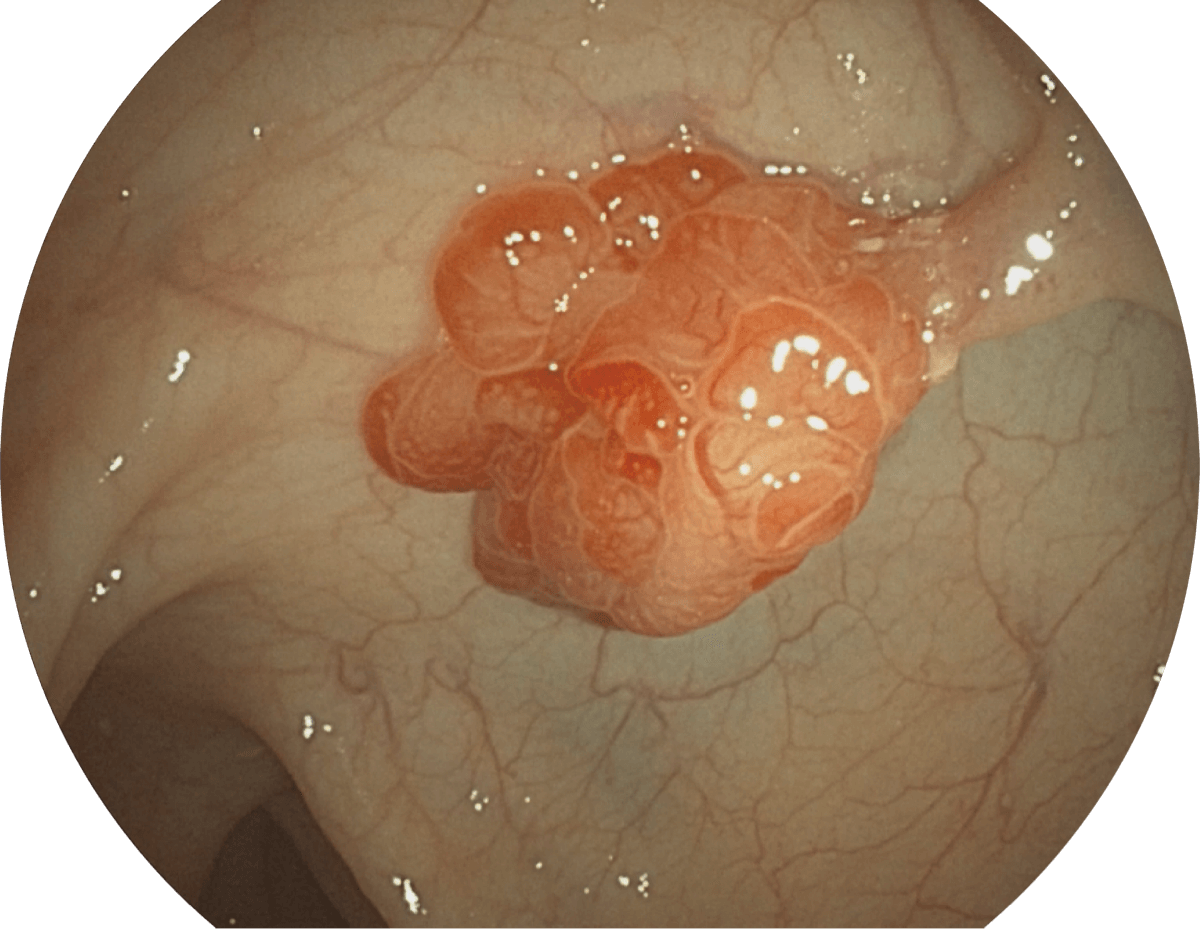

具有聚谱成像技术(SFI)及光电复合染色成像技术(VIST),可完美呈现粘膜细节及病变特征。

SFI

VIST